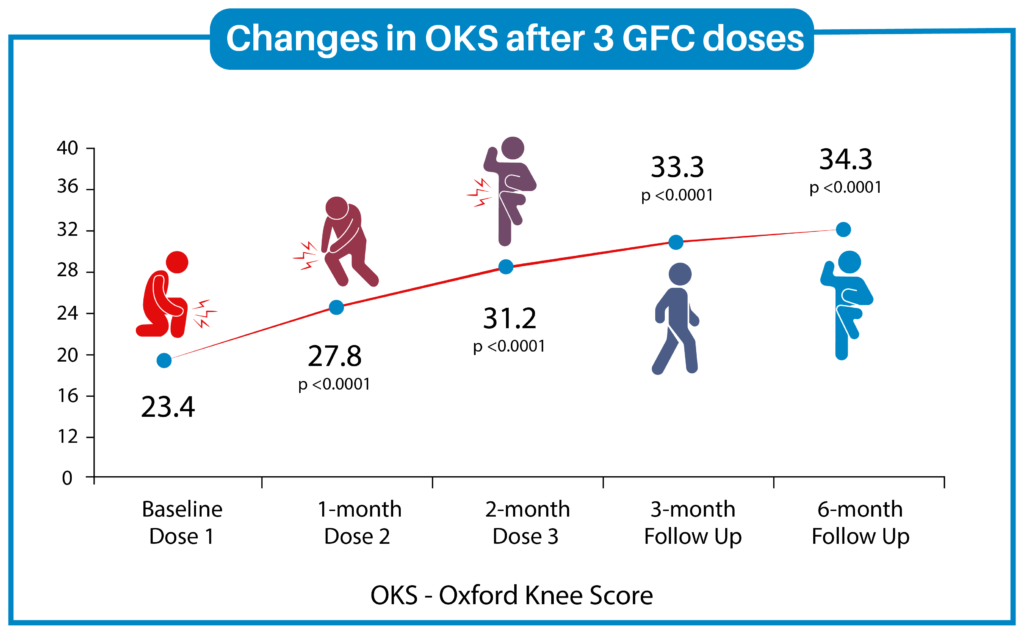

Results

Osteochondral defect – MRI Pre and Post